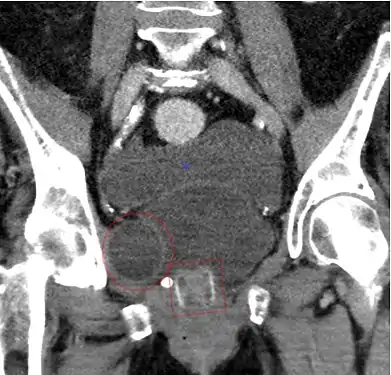

Tomografía computarizada (reconstrucción coronal) que muestra un AMS 800 en una mujer